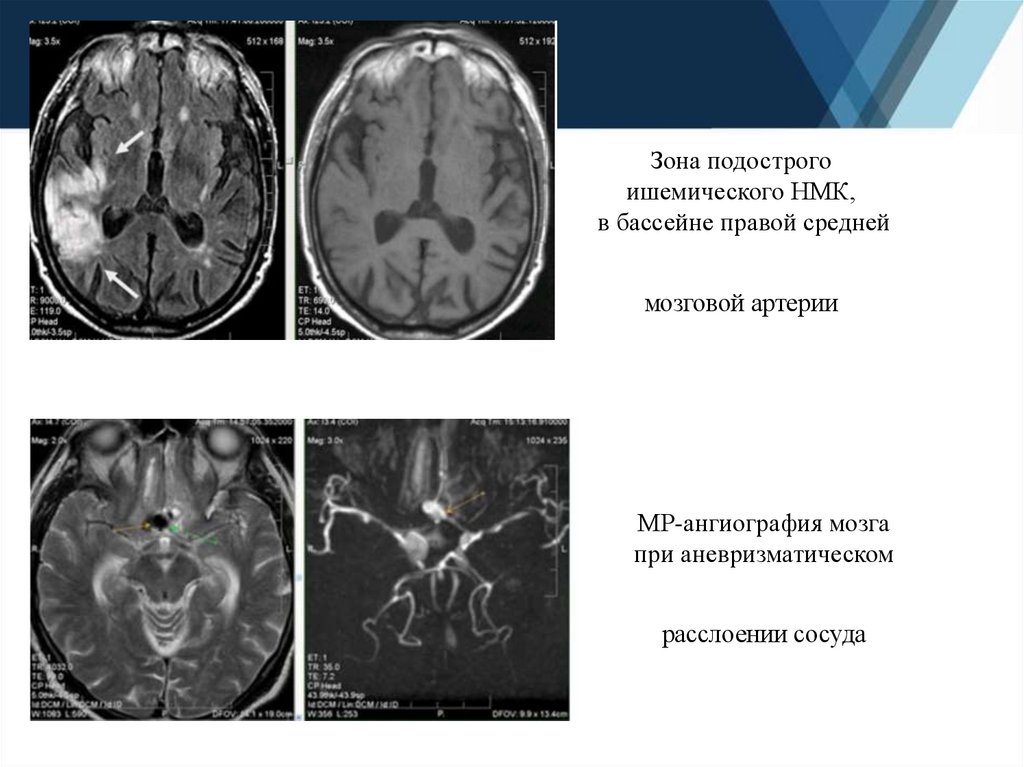

5.

Зона подострого

ишемического НМК,

в бассейне правой средней

мозговой артерии

МР-ангиография мозга

при аневризматическом

расслоении сосуда